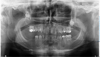

Mucosal involvement led to incomplete dental development. Agenesis affected teeth 32, 33, 37, 43, and 47, with impaction of 17, 18, 23, and 28. Crown and root dystrophy involved all other teeth except 35 and 45, and tooth 46 was missing (Fig. 3).

Fig. 3 Panoramic radiograph (April 2024) of case 2 revealing agenesis, short roots, and impacted teeth. |